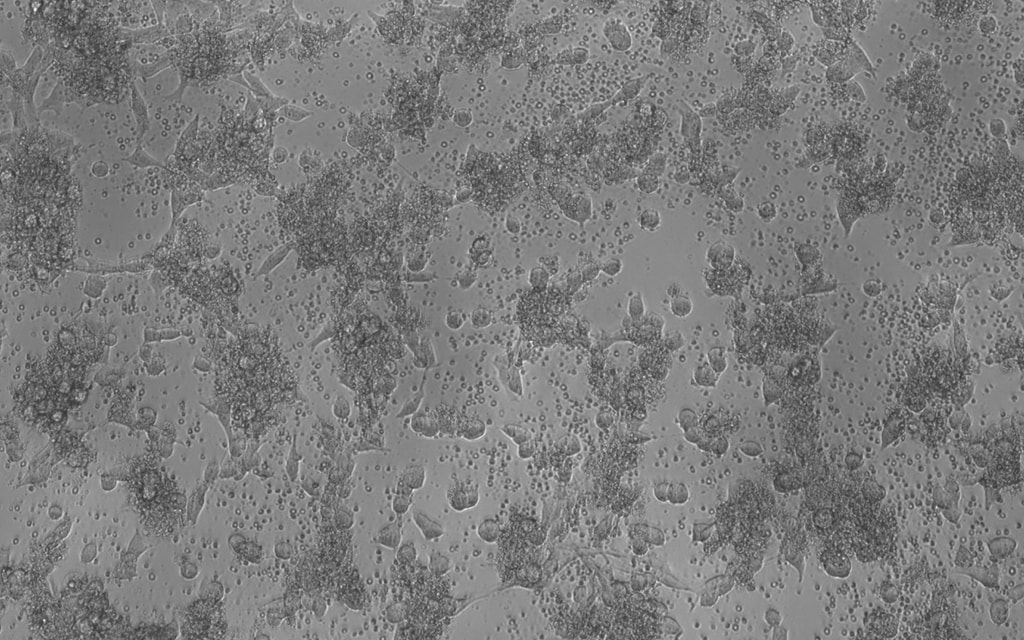

Our science is validated sufficiently, and we have clinical proof that Leukocyte-Tells (SL-28) works. Here is IRL imagery to show it.

Cancer cells

Leukocyte-Tells (SL-28)

result in tumor destruction